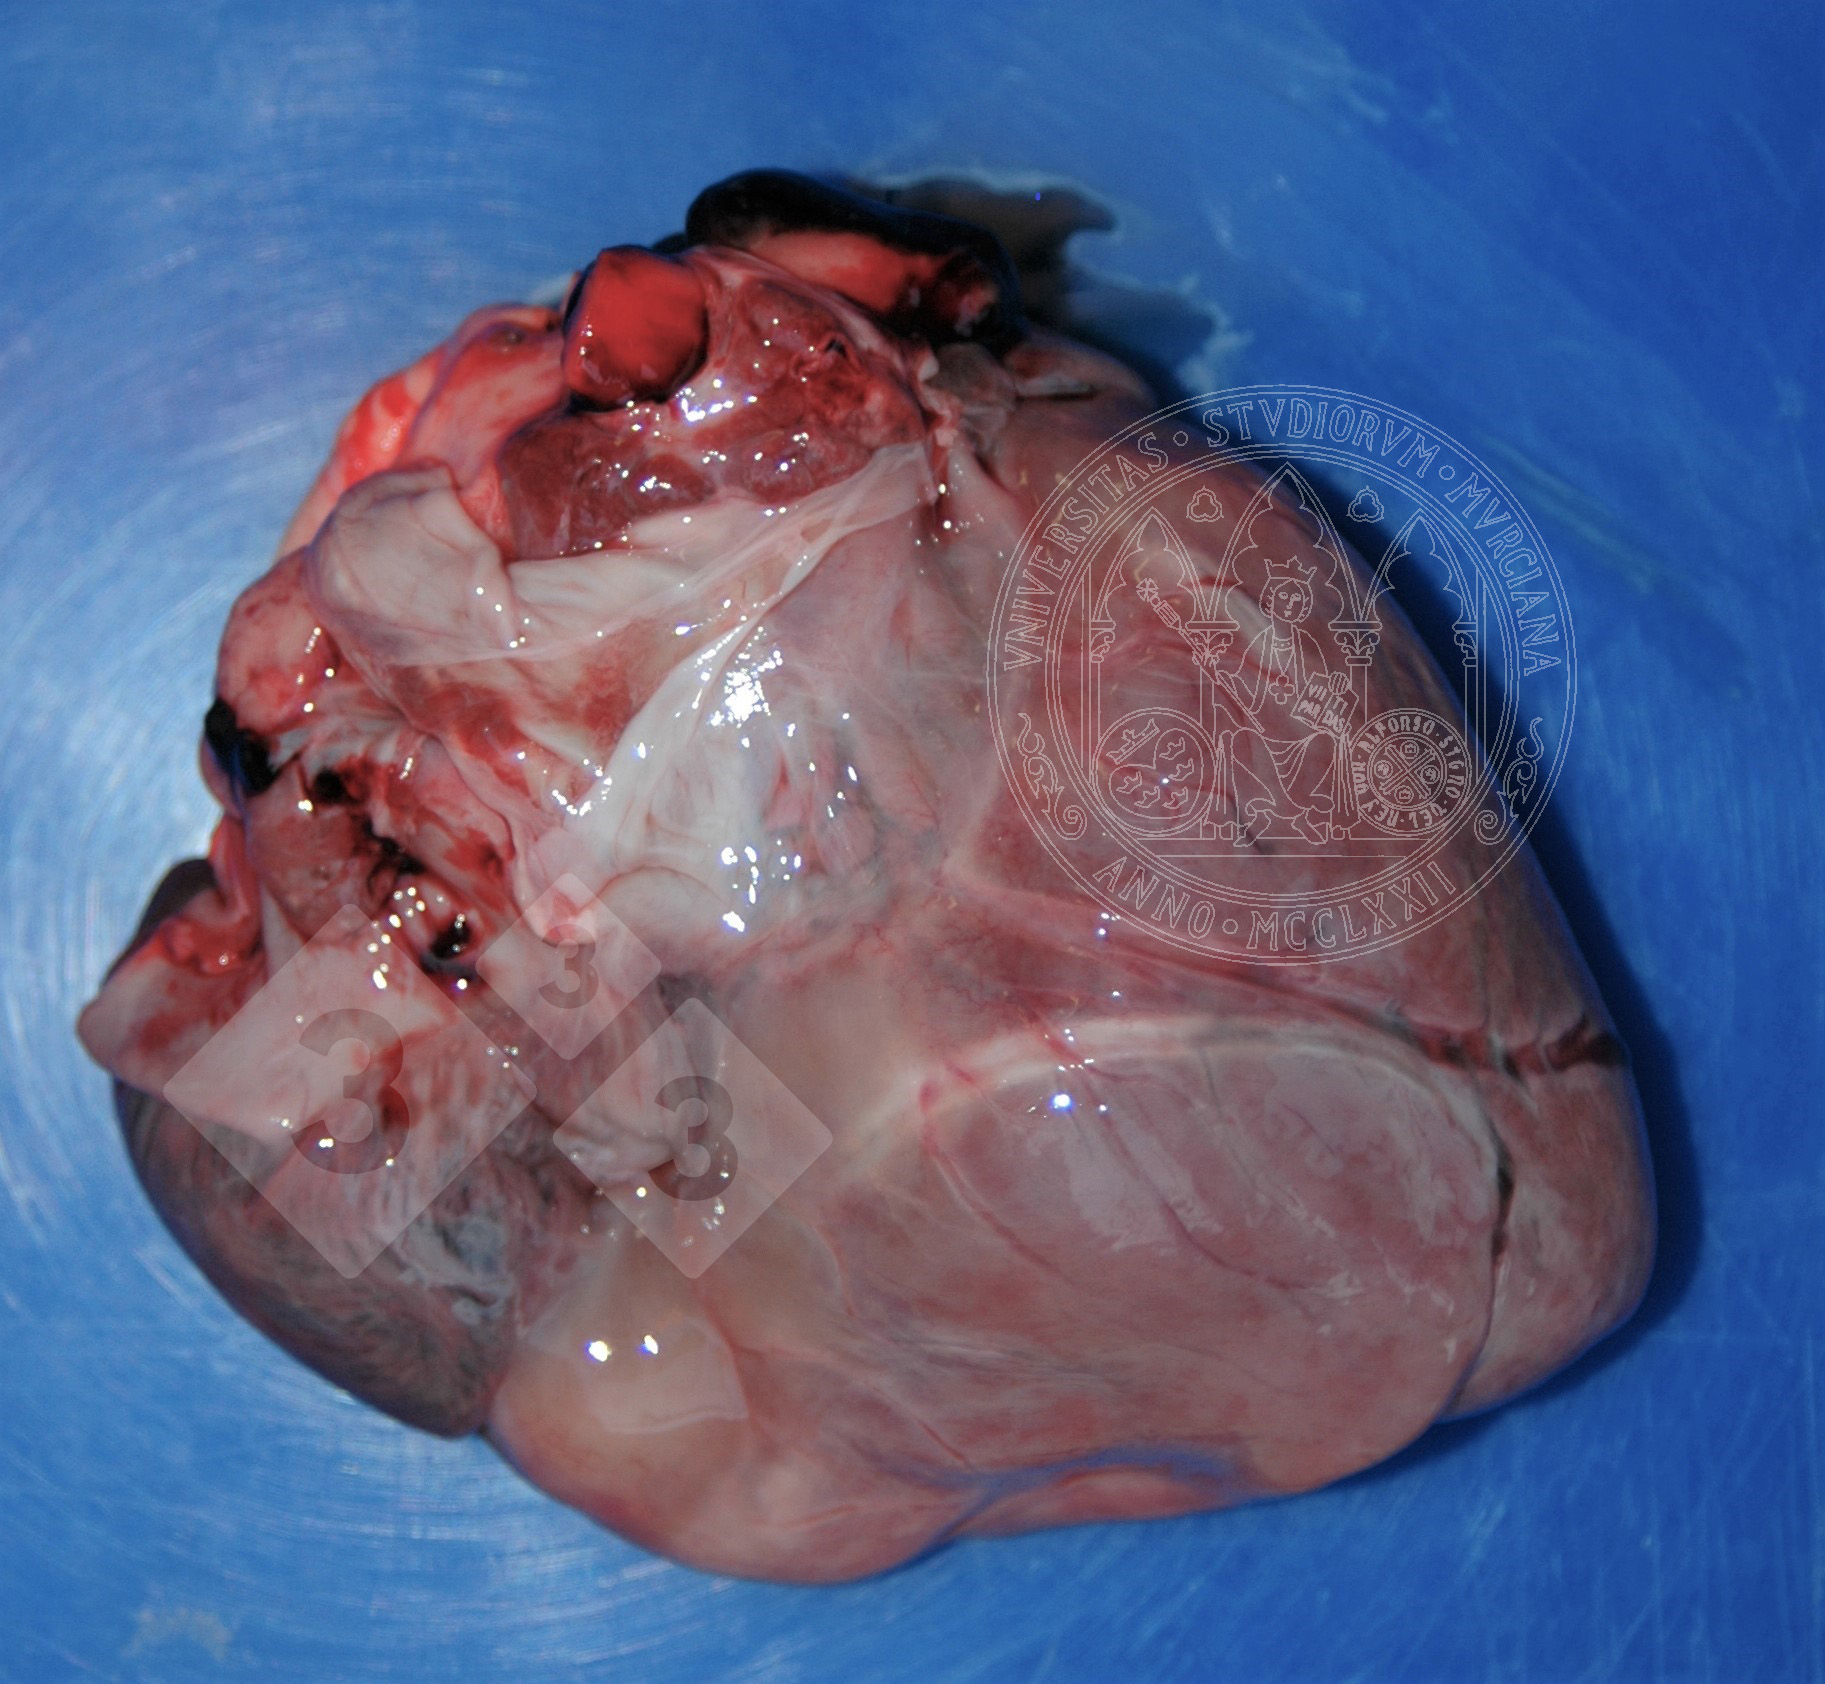

Atrofia sierosa del cuore - Atlante di patologia

Possiamo osservare questa lesione negli stati di cachessia. Per vari motivi può esserci una mobilizzazione del grasso di deposito, come quella nell'epicardio. I vacuoli lipidici diminuiscono di dimensioni e sono sostituiti da un fluido proteinaceo, mentre aumentano il liquido interstiziale, acquisendo un aspetto gelatinoso grigiastro. A volte si possono vedere anche piccoli focolai bianchi di necrosi adiposa.

Dobbiamo fare diagnosi differenziale con edema, di origine infettiva o no.